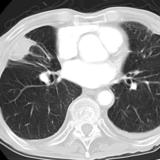

Rounded atelectasis case 2